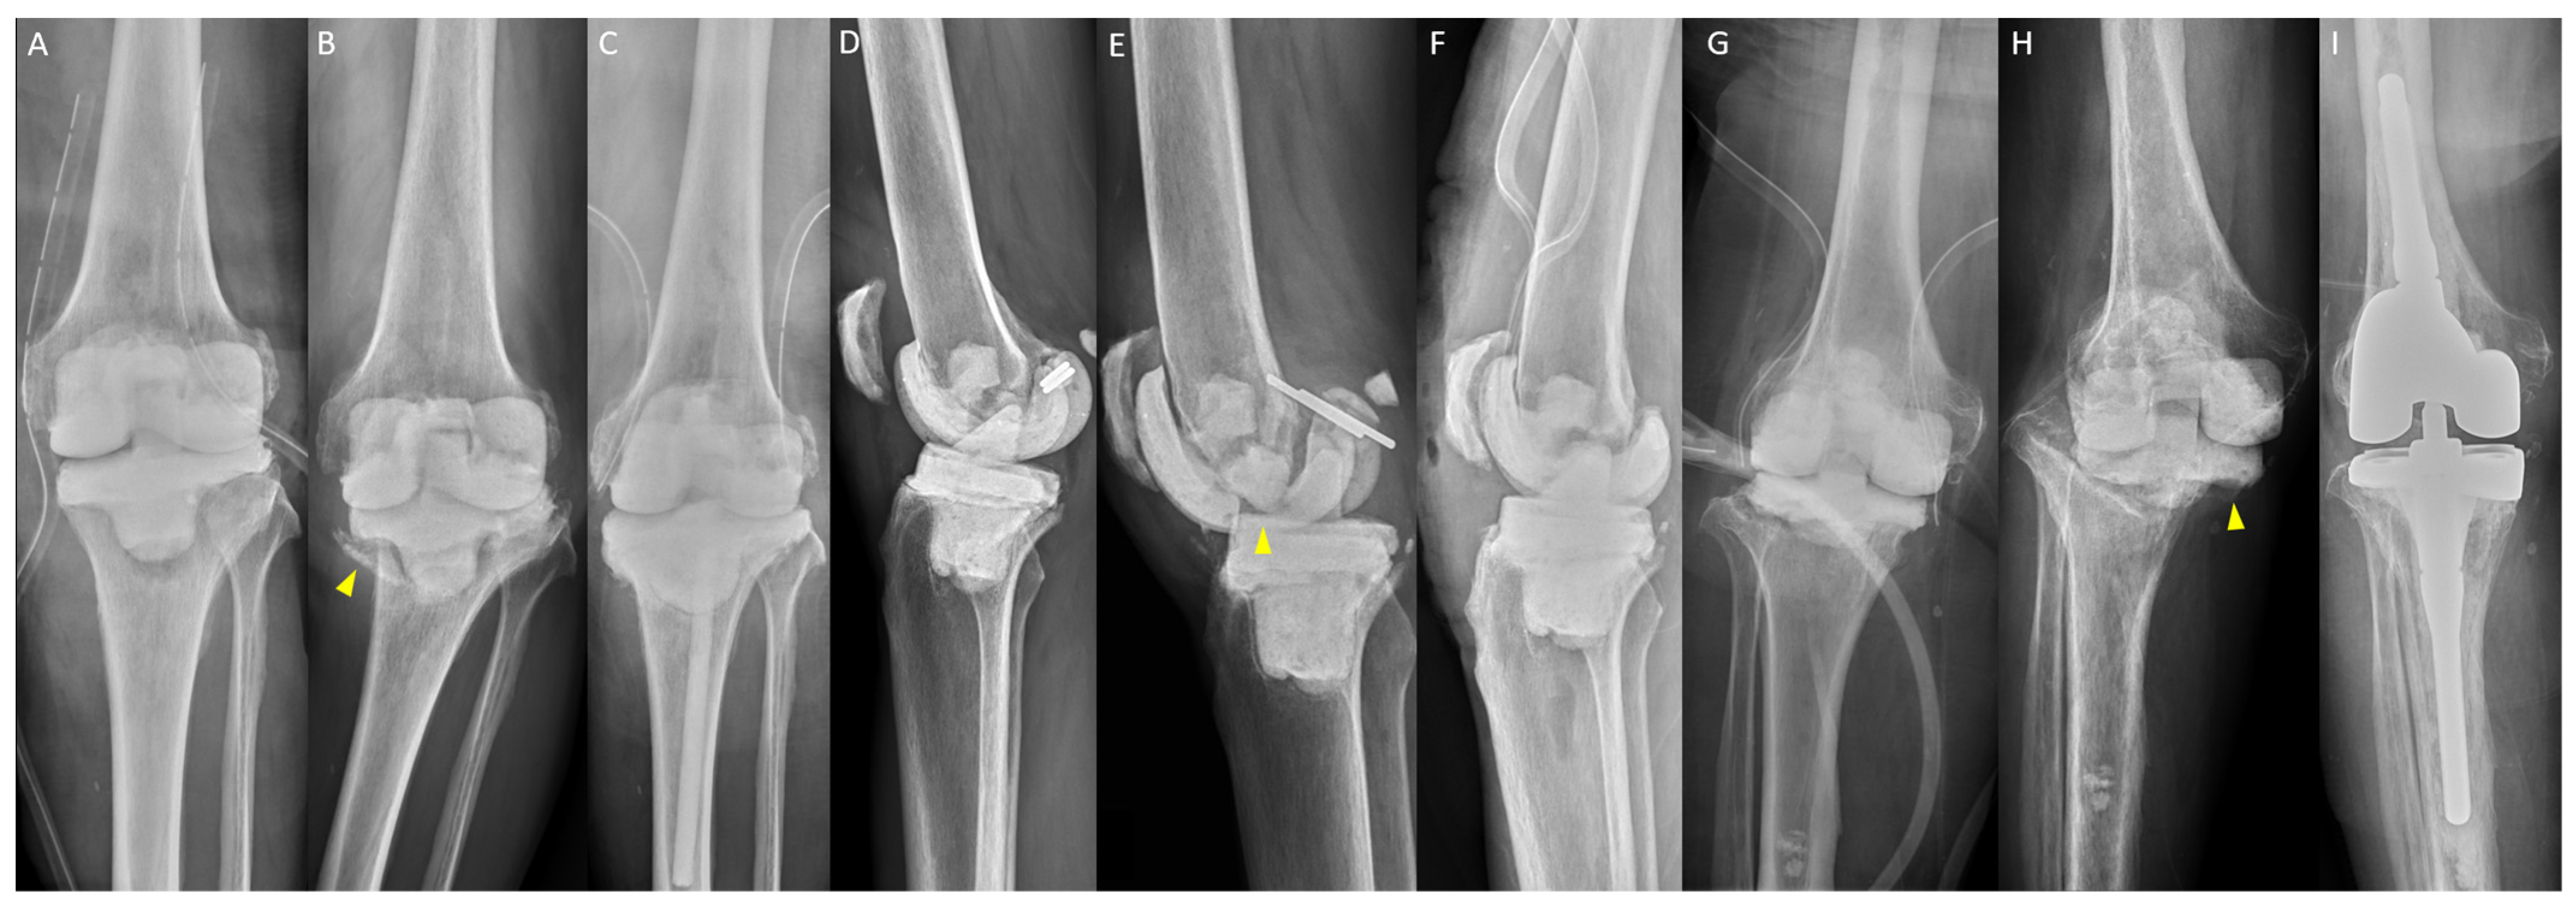

| Patient No. | Age (Years) | Sex | Radiographic Outlier | Mechanical Complication | Timing after Spacer (Weeks) | Intervention |

|---|---|---|---|---|---|---|

| LV surgeons | ||||||

| 1 | 73 | M | PTA < 87°; DFA < 92° | TS fracture | 2 | Hinge knee brace |

| 2 | 66 | M | PTA < 87°; DFA > 98° | Joint subluxation | 5 | Hinge knee brace |

| 3 | 82 | M | PTA < 87°; FS notching | Joint subluxation | 4 | Hinge knee brace |

| 4 | 63 | F | PTA < 87°; patellar maltracking | Joint dislocation | 4 | Open reduction |

| 5 | 66 | F | PTA < 87°; HKA < −10° | Joint subluxation | 3 | TS exchange |

| 6 | 86 | F | PTA < 87°; flexion contracture | Joint dislocation | 6 | TS exchange |

| 7 | 77 | F | PTA < 87° | Joint dislocation | 4 | TS exchange |

| 8 | 71 | M | PTA < 87°; FS without cement stem extension | Joint dislocation | 5 | TS exchange |

| 9 | 68 | M | PTA < 87° | Periprosthetic tibial fracture | 3 | TS exchange |

| 10 | 73 | M | PTA < 87°; flexion contracture | Periprosthetic tibial fracture | 4 | Both spacers exchange |

| 11 | 72 | F | PTA < 87°; HKA < −10° | Both spacers fracture | 6 | Unexpected early reimplantation |

| 12 | 68 | F | Recurvatum deformity; DFA > 98° | Joint subluxation | 5 | Hinge knee brace |

| 13 | 58 | M | Recurvatum deformity | Joint subluxation | 7 | Hinge knee brace |

| 14 | 72 | M | Recurvatum deformity; TS without cement stem extension | Joint dislocation | 4 | Both spacers exchange |

| 15 | 80 | F | Recurvatum deformity; TS overhang | Joint dislocation | 6 | Both spacers exchange |

| 16 | 66 | F | Recurvatum deformity; HKA angle < −10° | Joint dislocation | 7 | FS exchange |

| 17 | 60 | M | Recurvatum deformity; DFA < 92° | Joint dislocation | 4 | FS exchange |

| 18 | 80 | F | Recurvatum deformity; patellar maltracking | Joint dislocation | 8 | FS exchange |

| 19 | 67 | F | Recurvatum deformity; FS notching | Joint dislocation | 4 | FS exchange |

| 20 | 63 | M | Recurvatum deformity | FS fracture | 4 | Both spacers exchange |

| 21 | 60 | M | Recurvatum deformity; FS without cement stem extension | Periprosthetic tibial fracture | 6 | Unexpected early reimplantation |

| 22 | 61 | M | TS without cement stem extension | Joint subluxation | 4 | Hinge knee brace |

| 23 | 73 | F | TS without cement stem extension; DFA > 98° | Joint subluxation | 5 | Hinge knee brace |

| 24 | 61 | M | TS without cement stem extension | Joint dislocation | 3 | Both spacers exchange |

| 25 | 72 | M | TS without cement stem extension; DFA < 92° | Joint dislocation | 6 | Both spacers exchange |

| 26 | 75 | F | TS without cement stem extension; patellar maltracking | TS migration | 3 | TS exchange |

| 27 | 68 | F | TS without cement stem extension | TS migration | 4 | TS exchange |

| 28 | 69 | M | TS without cement stem extension; PSA > 90° | TS migration | 4 | Both spacers exchange |

| 29 | 73 | F | TS without cement stem extension; TS overhang | TS migration | 3 | TS exchange |

| 30 | 60 | F | TS without cement stem extension; HKA angle < −10° | TS migration | 5 | TS exchange |

| 31 | 66 | M | TS without cement stem extension; PTA > 93° | TS migration | 3 | TS exchange |

| 32 | 76 | F | TS without cement stem extension | TS migration | 6 | Unexpected early reimplantation |

| 33 | 77 | F | TS overhang; DFA > 98° | Extensor mechanism disruption | 3 | TS exchange |

| 34 | 67 | M | Patellar maltracking; DFA < 92° | Extensor mechanism disruption | 4 | Lateral release |

| 35 | 64 | F | HKA < −10°; DFA < 92° | TS migration | 6 | Unexpected early reimplantation |

| 36 | 72 | F | HKA < −10°; flexion contracture | Both spacers fracture | 3 | Hinge knee brace |